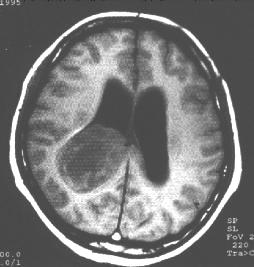

右侧脑室三角区室管膜瘤。MR横断面右侧脑室三角区肿块,已累及周围脑实质,T1加权(上图)示病灶大部分呈略低信号,中间见低信号的坏死区,T2加权(中图)病变呈高信号,增强后(下图)病变呈不规则不均匀强化。 | |